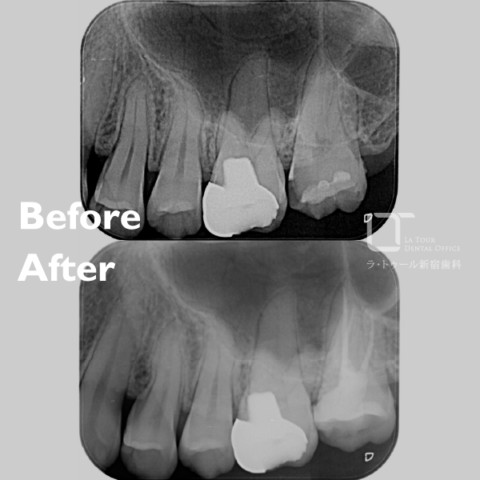

精密根管治療の治療例です。「以前の詰め物を外して治療してほしい。たまに噛むと違和感がある」とのことで来院されました。当院にて診査・診断を行い、専門医による精密根管治療を実施しました。

治療前と治療後の比較